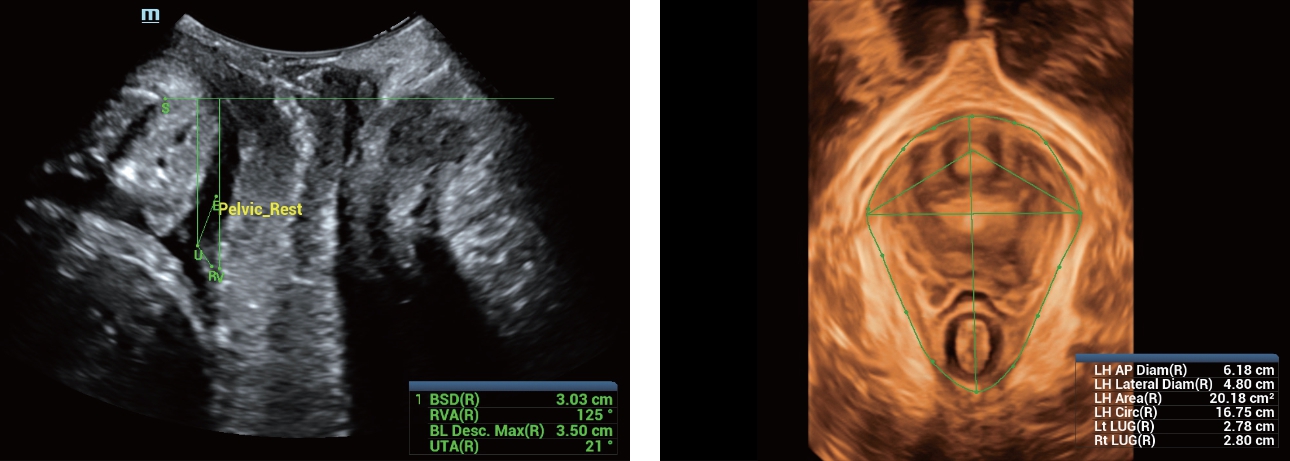

Desde que a empresa foi fundada, a Mindray est├Ī continuamente explorando novas maneiras de melhorar a confian?a no diagn├│stico. Alimentada pela mais revolucion├Īria tecnologia ZONE Sonography?, a nova plataforma Resona 7's ZST+ traz uma qualidade de imagem ultra-som a um n├Łvel superior por aquisi??o de zona e processamento de dados do canal.

Assim como o n├Łvel de qualidade de imagem premium, o Resona 7 tamb├®m melhora as capacidades de investiga??o cl├Łnica com o revolucion├Īrio Fluxo V para avalia??o hemodin?mica vascular e a aquisi??o de plano mais inteligente do conjunto de dados 3D para diagn├│stico CNS fetal. Combinando a opera??o mais intuitiva baseada em gesto de multi-toques e todos os recursos cl├Łnicos essenciais, Resona 7 est├Ī realmente conduzindo novas ondas na inova??o de ultra-som.